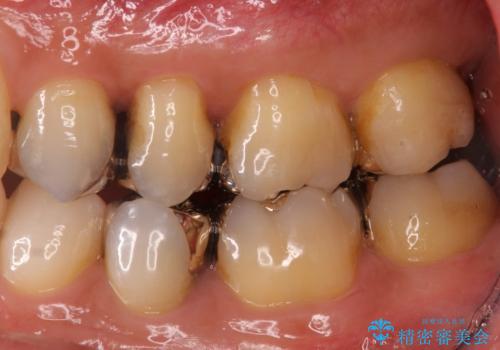

- 銀歯をすべてやり替えたいとのことで来院された患者様です。

再根管治療が必要なところは再根管治療から、そうでないところは補綴物のみをやり替えていくこととなりました。

銀歯のやり替えと並行してホワイトニングも行いました。

結果的には銀歯がすべて白くなり、前歯のガタつきもある程度改善され大変喜んでいただけました。